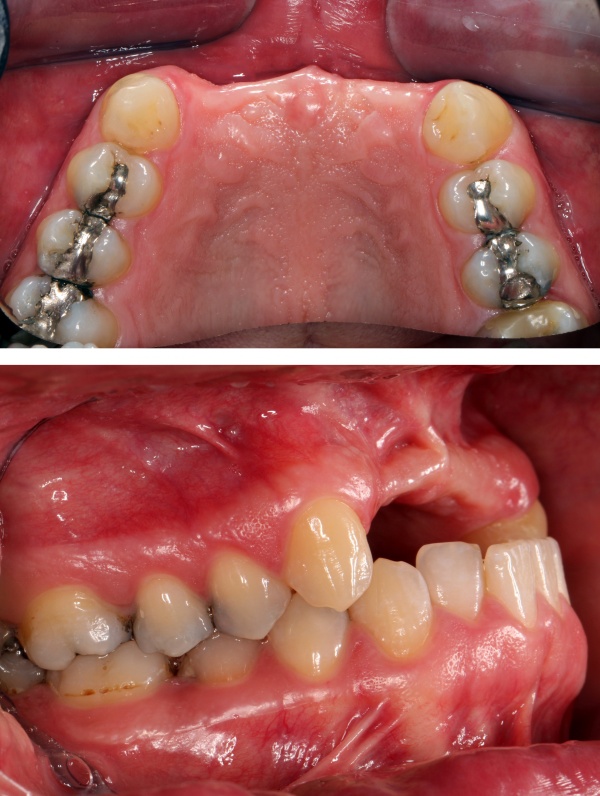

Ein 31jähriger Patient stellte sich am 10.11.2011 in der Implantatsprechstunde vor mit der Bitte um Befürwortung einer implantatgetragenen prothetischen Lösung für eine seit 1997(!) bestehende Schaltlücke 12 bis 22 nach tätlicher Auseinandersetzung.

Die Lücke war bis dato über eine insuffiziente Teilprothese versorgt. Es bestand eine ausgeprägte Oberkieferatrophie in allen Dimensionen mit negativer Stufe im Verhältnis Oberkiefer zu Unterkiefer (Bild) sowie Elongation der Unterkieferfrontzähne (Abb. 9).

Zur Wiederherstellung von Phonetik und Ästhetik und Verhinderung einer weiteren Elongation der Unterkieferzähne wurden für die Rekonstruktion der Oberkieferfront 4 Einzelzahnimplantate beantragt nach vorheriger Augmentation von Beckenkamm.

Zum Ausgleich der konsekutiv vorliegenden Weichgewebsatrophie erfolgte im Juni 2012 nach Genehmigung des Antrags durch das Sanitätsamt der Bundeswehr zunächst die Implantation von 2 Weichgewebsexpandern (Firma Osmed) im Oberkiefer (Abb. 10). Nach Schaffung eines adäquaten Weichgewebsbettes wurde im Juli 2012 zur Korrektur der extremen Hartgewebsatrophie eine Augmentation vom Beckenkamm durchgeführt (Abb. 11). Im Dezember 2012 erfolgten in Lokalanästhesie nach ungestörter Einheilung die Materialentfernung der Osteosyntheseschrauben und die Implantation von 4 dentalen Implantaten (Firma Nobel Biocare, Replace straight, Abb. 12). Durch Atrophie und die rekonstruktiven Operationen bedingt, wurde zur Korrektur der ungenügenden Weichgewebsverhältnisse eine Vestibulumplastik nach 3 Monaten mit Einlagerung einer bioresorbierbaren Membran (Firma Botiss, Mucoderm) durchgeführt. Nach weiteren 3 Monaten erfolgte die Freilegung der Implantate (Abb. 13) mit einer Rolllappenplastik an jedem Implantat zur vestibulären Rekonturierung der Schleimhaut.